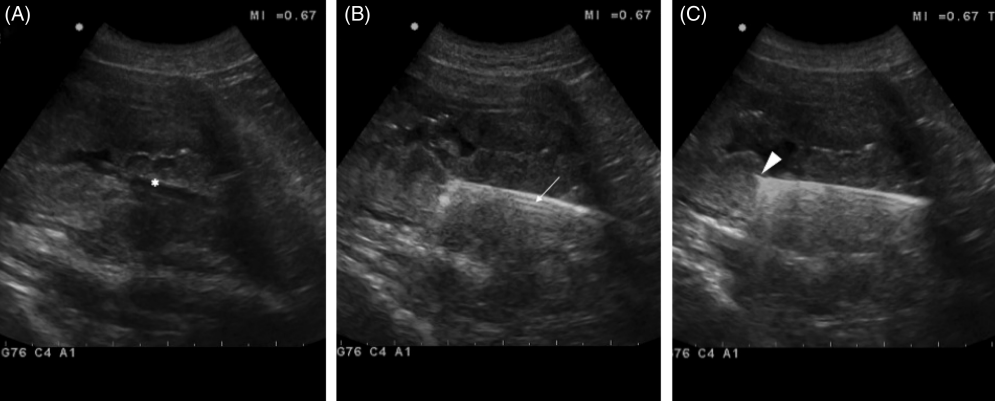

초음파와 내시경 포셉을 이용한 방광 조직생검 방법

내시경 검사를 할때 위장관 조직을 생검하던 바이옵시 포셉을 이용하여 방광내 TCC와 같은 종양을 조직 생검하는 방법에 대한 논문

당연히 샘플링 위치는 초음파 유도하에 한다.